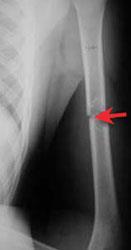

Humerus (upper arm) tumor and pathologic fracture

Humerus (upper arm) tumor and fracture. This X-ray shows a fracture through a tumor in the middle of the bone of the upper arm.